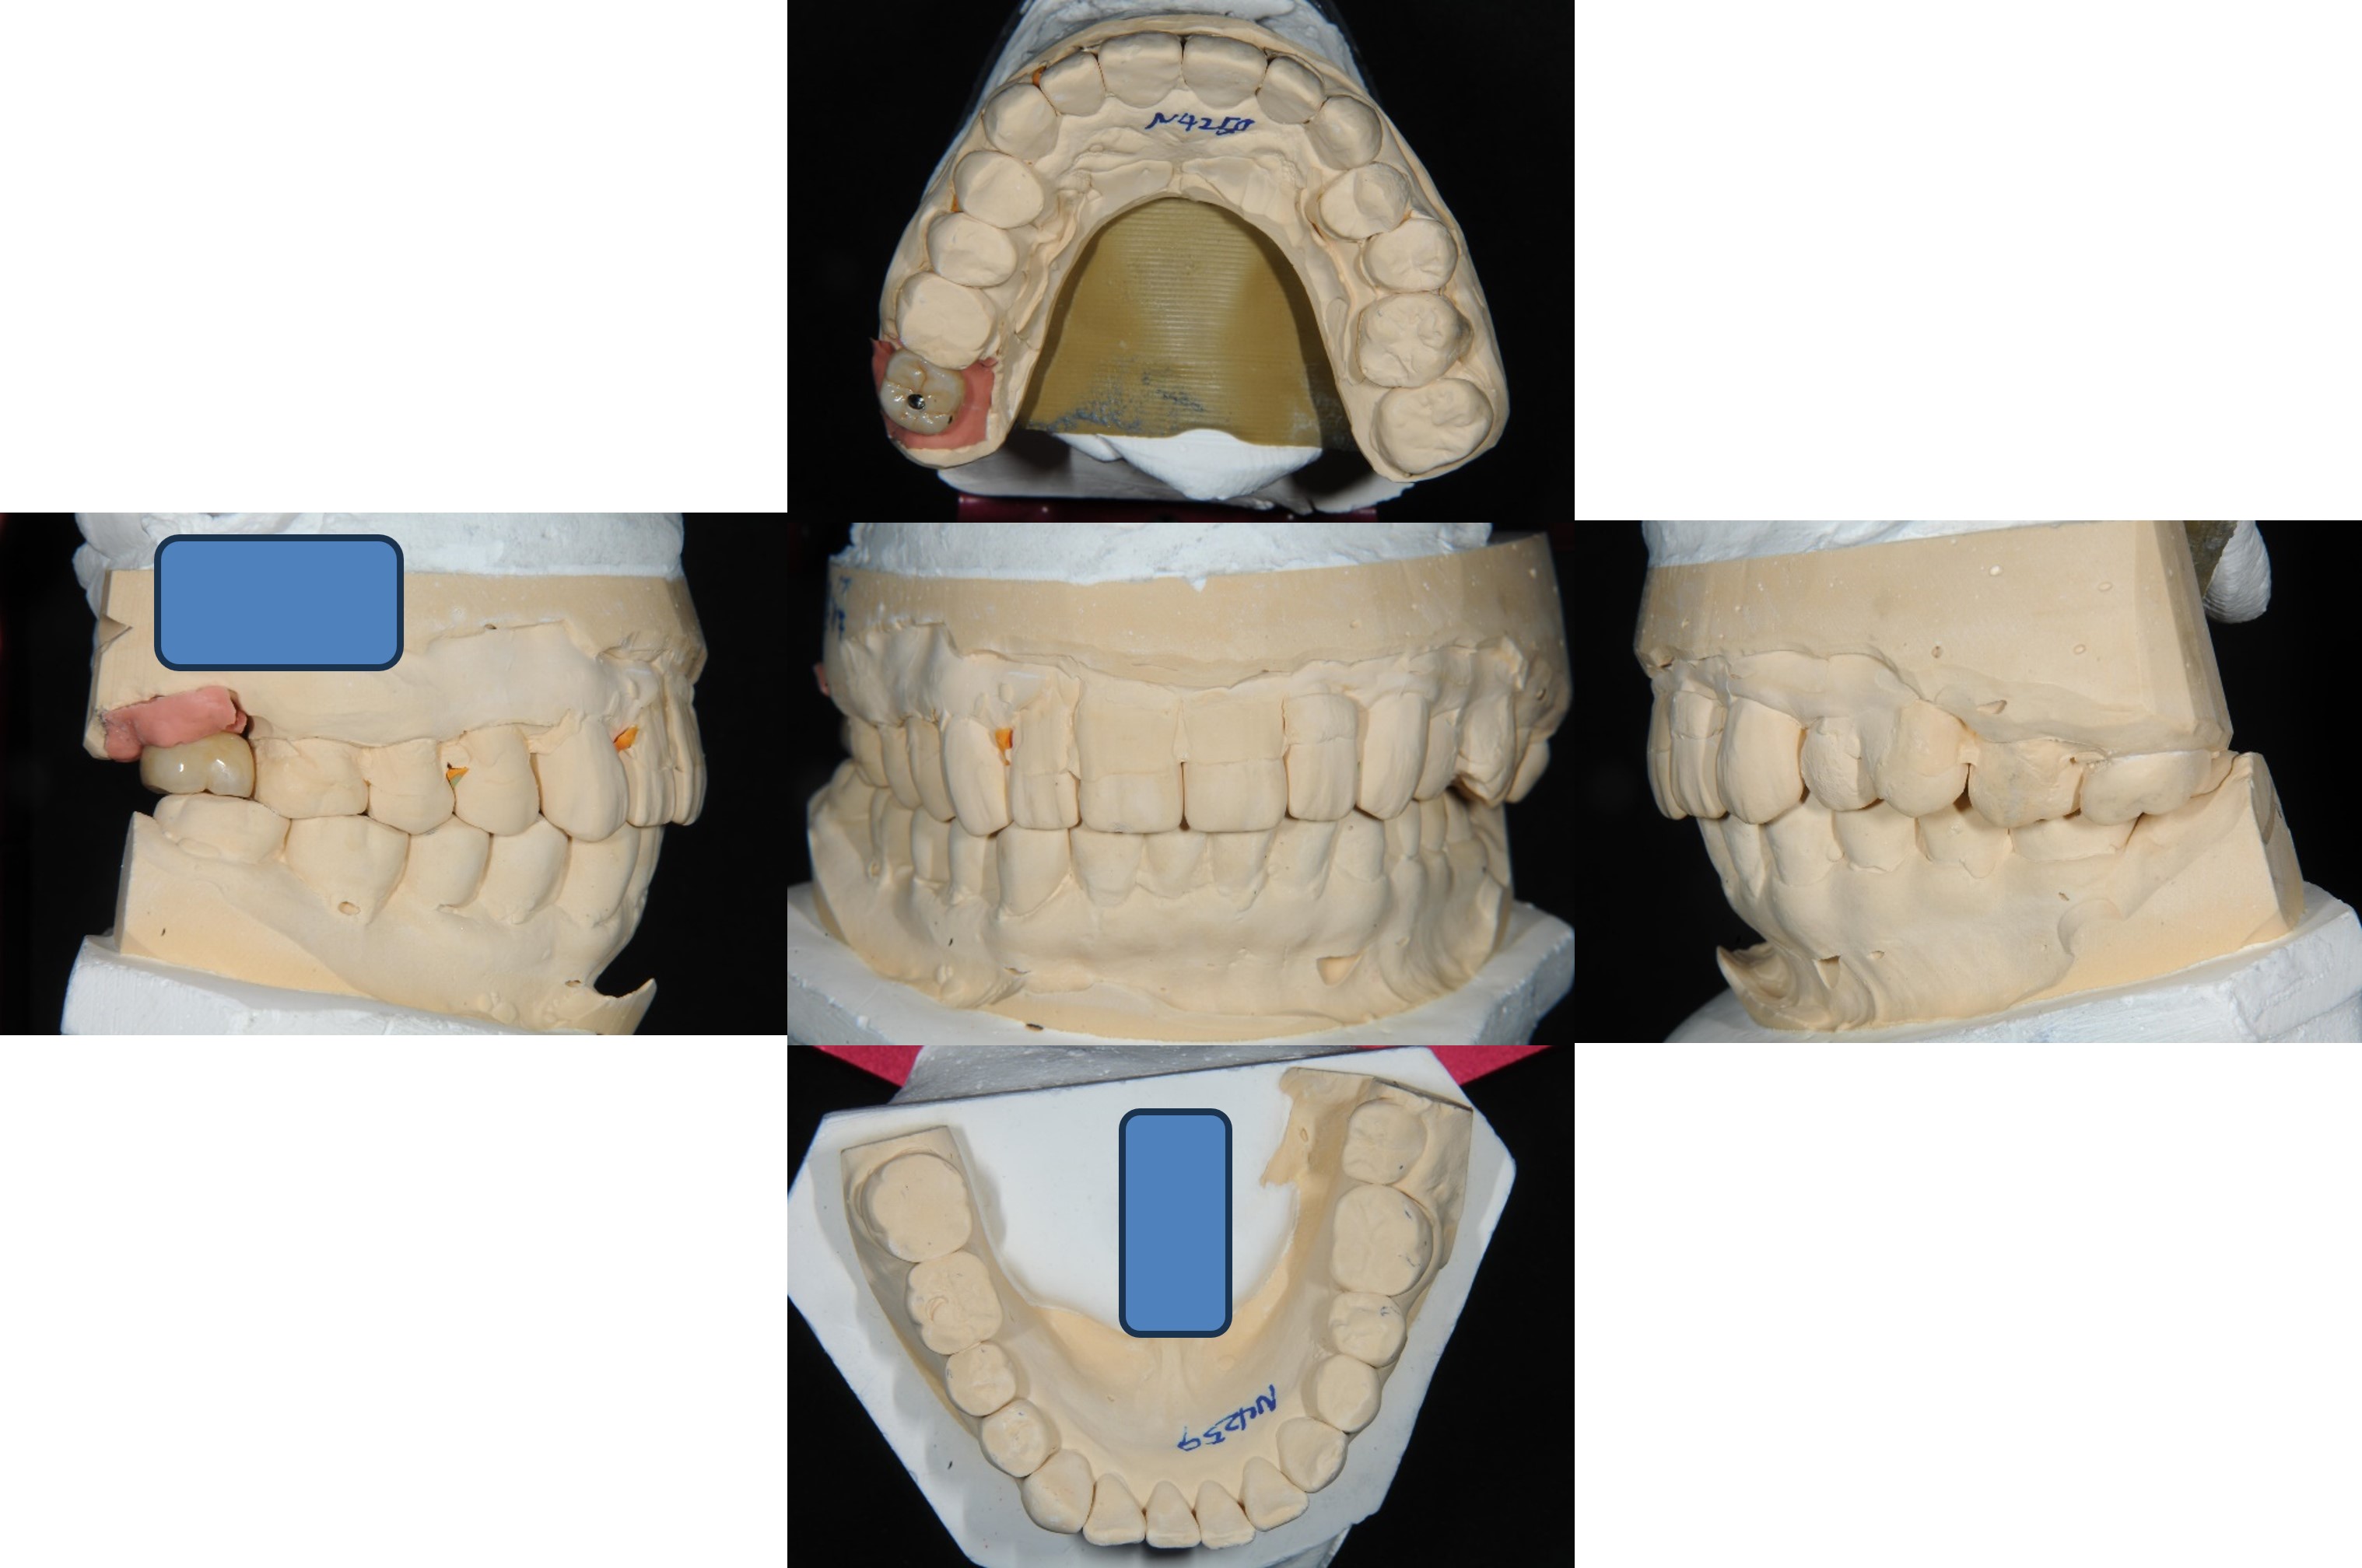

植牙規畫模擬

面弓轉移,上咬合器

咬合器上製作瓷牙